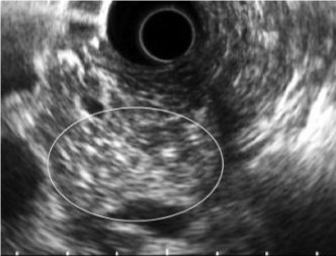

EUS Features of Chronic Pancreatitis

CP is characterized by fibrosis of parenchyma along with ductal changes in the pancreas. These changes of fibrosis have been characterized as hyperechoic using ultrasound [11-13]. The superiority of EUS is not so high in the case of advanced CP because typical CP findings such as atrophy, calcification, main duct dilation, duct irregularity, cyst are readily observed even using other modalities. However, it is difficult to observe minute changes of pancreatic parenchyma using means other than EUS. Among patients with chronic pancreatitis, EUS will reveal all pancreatic abnormalities. Typical EUS findings are shown in figures 2-6.